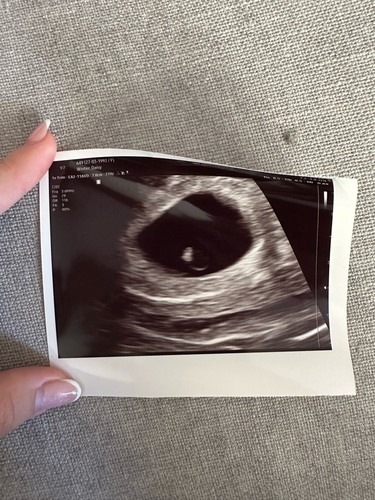

Ik heb met 5+6 een echo gehad bij m'n vorige zwangerschap en zag ook een hartje :-) Heeel klein weliswaar, maar onmiskenbaar een dooierzakje + mini. Tussen de streepjes is het vruchtje. Succes 🍀 Fijn dat je wat eerder langs mag komen! Grote kans dat je na 1-2 weken nog eens mag zodat ze de vitaliteitsecho kunnen doen. Dat had ik in het ziekenhuis (toen was ik nog medisch) wel namelijk.